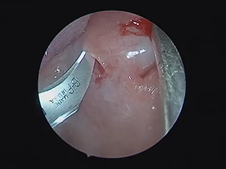

Microdirect Laryngoscopy and CO2 Laser Total Vestibulectomy for Pyolaryngocele

- Date : 01/01/2020